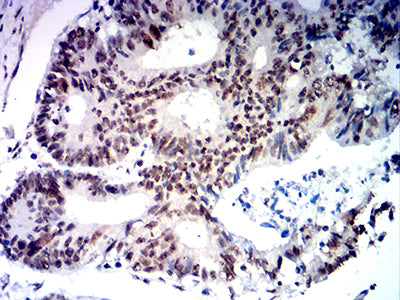

分类: 科研抗体货号: 31876别名: FCC2; COCA2; HNPCC; hMLH1; HNPCC2应用: IHC,FCM反应种属: Human